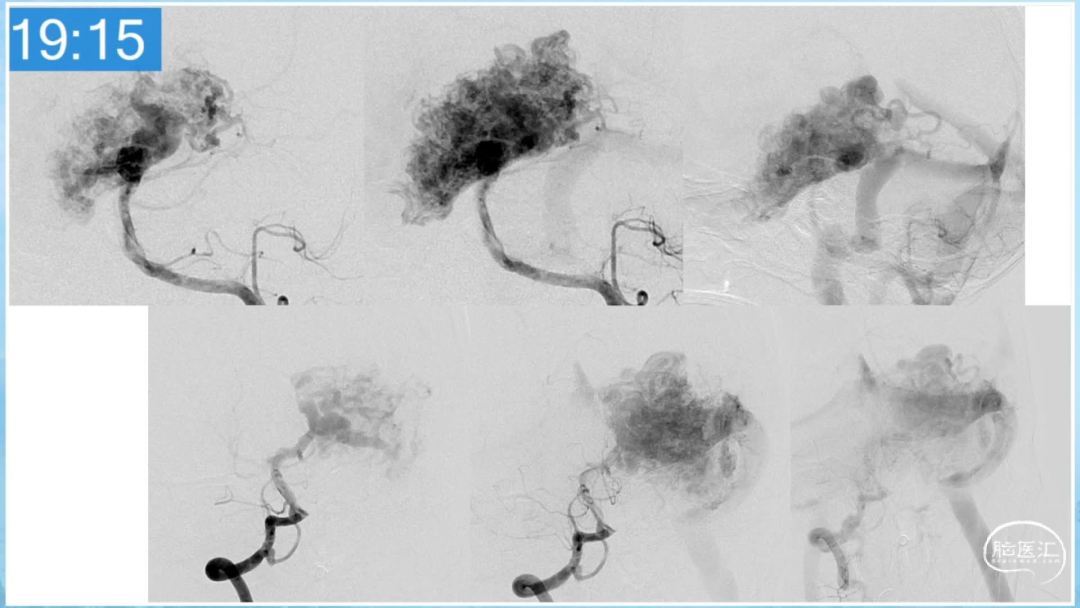

合理的复合平台下的综合治疗,针对每一个病变对应不同方法安全性分析,不预设、不排斥,每种技术发挥到最佳,互相保障。